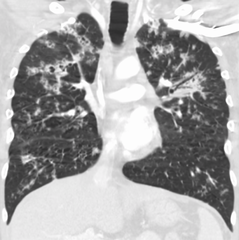

CT, showing extensive pulmonary parenchymal involvement consisting of irregular septal thickenings with ground-glass areas and centrilobular nodules with a peri-lymphatic distribution